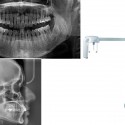

Dental Imaging – X-ray technology allows dentists to diagnose and treat dental problems not yet visible to the naked eye, including early tooth decay, gum disease, abscesses and abnormal growth. It is almost impossible to imagine the practice of dentistry without x-ray pictures (radiographs).This diagnostic tool has prevented untold suffering and saved countless teeth.

Dental X-Ray & Imaging Centre is among the leading Digital Dental Imaging Service Providers in Nairobi, Kenya. This digital x-ray technology uses a small electronic sensor placed in the mouth to capture an image, which can be called up instantly on a computer screen.

• Offers better & more reliable imaging results/picture. Digital x-rays enable our experienced provider to instantly detect abnormalities in teeth, gums, enamel as well as tumorous masses, cavities & hidden dental structures

• Gray-scale resolution of 256 colors compared to 16 to 25 shades on conventional film, allowing for a more detailed, accurate analysis

• Images can be enlarged, adjusted, and saved for future reference

Digital Imaging is the ability of the operator to post-process the image. Post-processing an image allows the operator to manipulate the pixel shades to correct image density and contrast. Images can be stored in a computer and can be viewable on the same computer screen or be printed on paper or film. The images can be viewed in more than one room and can be used in conjunction with pictures obtained with an optical camera to enhance your understanding of treatment.